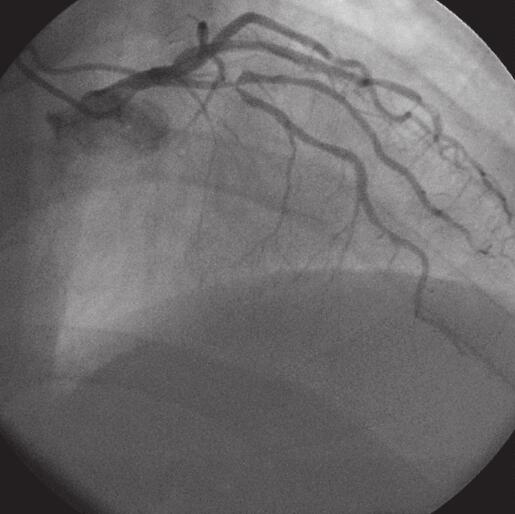

六、介入诊治情况

于入院后第10日患者行冠状动脉造影术+PCI术。取右侧桡动脉途径,冠状动脉造影,显示为右优势型,左主干未见有意义狭窄;前降支近端于第一对角支发出处99%狭窄,第一对角支开口99%狭窄;旋支未见有意义狭窄;右冠状动脉开口以远99%局限狭窄病变,后分叉前85%局限狭窄,考虑到患者前降支及右冠状动脉病变均较重,而此次梗死相关动脉为右冠状动脉,故决定先行右冠状动脉PCI术,择期行LAD PCI术。行右冠状动脉造影时心电监护出现一过性三度房室传导阻滞,故穿刺右股静脉成功后植入6F鞘管,沿鞘管送入起搏电极达右室心尖部备用,于右冠状动脉病变处植入2枚支架。术中心电监护为一度、二度房室传导阻滞,未再出现三度房室传导阻滞。1周后于前降支处再次行PCI术,植入1枚支架(图2-16-1~图2-16-5)。

图2-16-1 前降支PCI术前1

图2-16-2 前降支PCI术前2

图2-16-3 前降支PCI术后

图2-16-4 右冠状动脉PCI术前

图2-16-5 右冠状动脉PCI术后